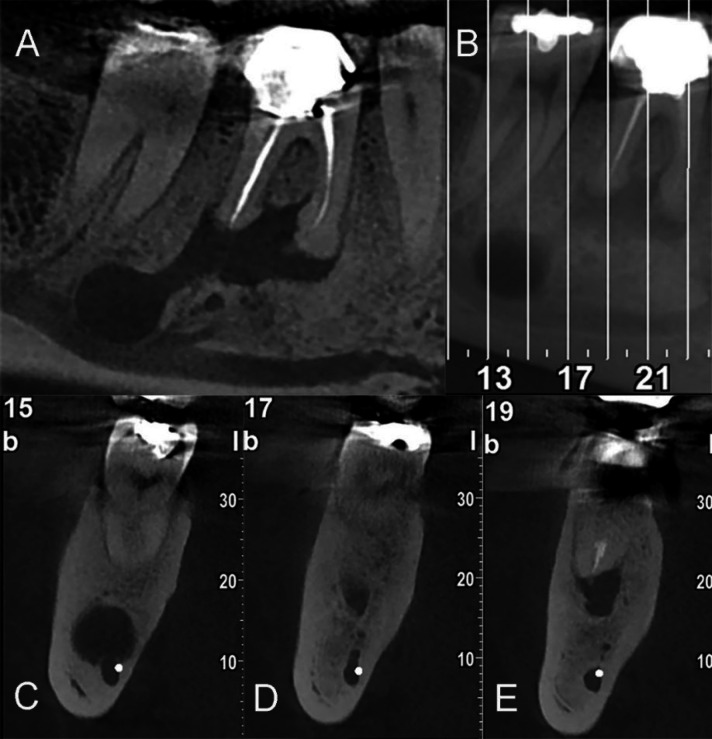

本病例报告旨在记录一名 35 岁男性患者的罕见远端牙源性病变,该患者下颌右侧第一磨牙有轻微的临床不适;探讨了不常见的远端牙髓病变的诊断和治疗的复杂性,最终通过细致的非手术再治疗得到了解决。尽管口腔检查结果正常,但放射诊断检查却显示根管治疗效果不佳,根尖中、远端病变环绕根尖;包括通过全景放射检查发现的下颌第二磨牙根尖下方的明显放射线,并经锥形束计算机断层扫描证实。此外,计算机断层扫描还发现了一个以前从未报道过的、异常巨大的牙髓病变,该病变向下颌管延伸;这凸显了继续探索这一独特牙髓病变的必要性。非手术的牙髓再治疗使放射状病变在一年内显著缩小;强调了综合诊断方法和个体化治疗的重要性。

The current case report aims to document a rare presentation of a distant odontogenic lesion of a 35-year-old male patient with mild clinical discomfort in the mandibular right first molar; exploring the diagnostic and therapeutic intricacies of an uncommon distant endodontic pathosis ultimately resolved through meticulous nonsurgical retreatment. Despite a normal oral examination, diagnostic radiography revealed a suboptimal root canal treatment and apical lesions surrounding mesial- and distal-root apices; including a distinct radiolucency beneath the apex of the second mandibular molar discovered through panoramic radiography, and confirmed via cone-beam computed tomography. In addition, the computed tomography disclosed a previously unreported and unusually large endodontic lesion that extended toward the mandibular canal; highlighting a necessity for the continued exploration of a unique endodontic presentation. A nonsurgical endodontic retreatment led to a remarkable reduction in the radiolucent lesions within one year; emphasizing the significance of comprehensive diagnostic approaches and individualized treatments.